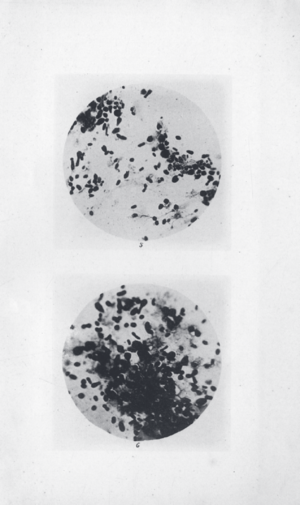

Y. pestis isolated by Ricardo Jorge (pt) during the 1899 Porto plague outbreak

In 1894, two bacteriologists, Alexandre Yersin of Switzerland and Kitasato Shibasaburō of Japan, independently isolated in Hong Kong the bacterium responsible for the Third Pandemic. Though both investigators reported their findings, a series of confusing and contradictory statements by Kitasato eventually led to the acceptance of Yersin as the primary discoverer of the organism. Yersin named it Pasteurella pestis in honor of the Pasteur Institute, where he worked. In 1967, it was moved to a new genus and renamed Yersinia pestis in his honor. Yersin also noted that rats were affected by plague not only during plague epidemics, but also often preceding such epidemics in humans and that plague was regarded by many locals as a disease of rats; villagers in China and India asserted that when large numbers of rats were found dead, plague outbreaks soon followed.[citation needed]